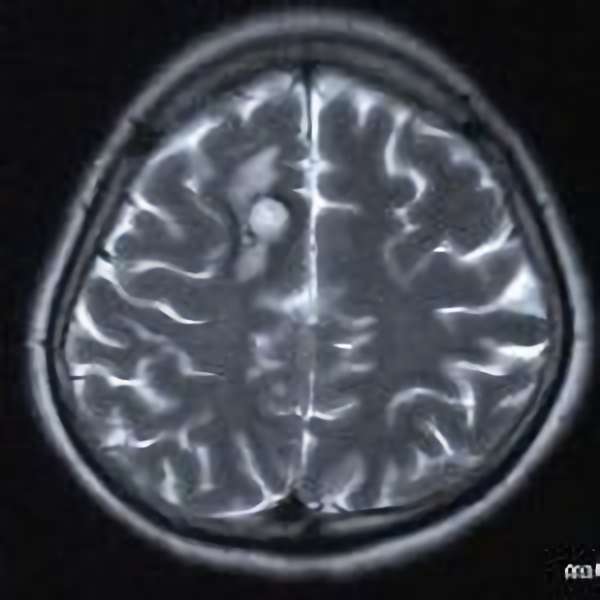

No.452 手術前